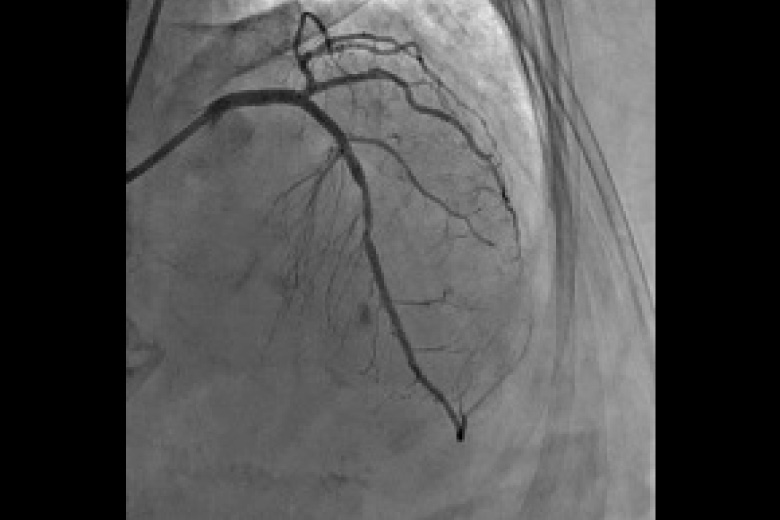

血管の中に造影剤を注入して脳、心臓、肝・胆道・膵、腎、四肢などの血管を造影診断、治療します。 心臓を中心とし検査を行う装置と腹部を中心とした検査をおこなう装置(IVR-CT)にて検査、治療をおこなっております。 心臓検査ではバイプレーン(2管球)装置のため少ない造影剤で検査を受けることができます。また腹部装置は80列CTとの組み合わせのためより高精細な画像が収集でき3Dガイド下にて検査・治療を行っています。

心臓用アンギオ装置 INFINIX Celeve I

冠動脈狭窄 治療前

冠動脈狭窄 治療後